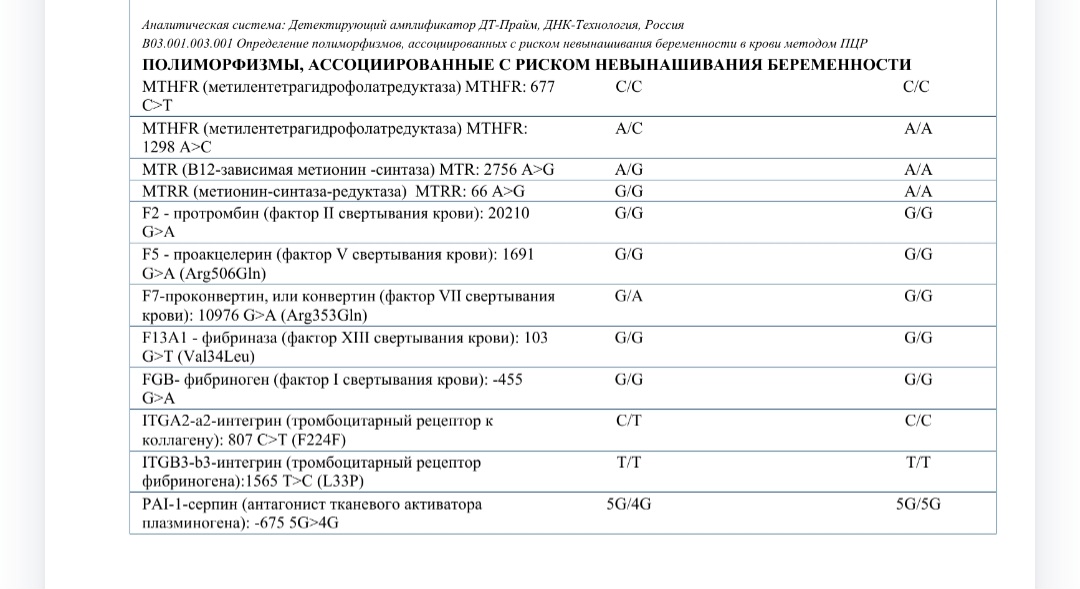

Расшифровка результатов анализа на полиморфизмы невынашивания беременности